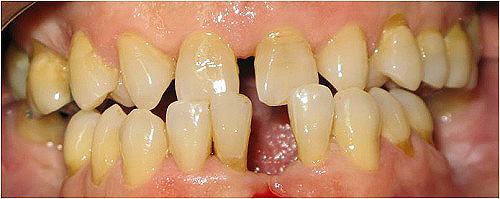

Caso 5 - Colocação de implantes dentários e reabilitação com pontes em zircónio cerâmica para reabilitação dos dentes ausentes do 3º e 4º quadrantes.

![]() |